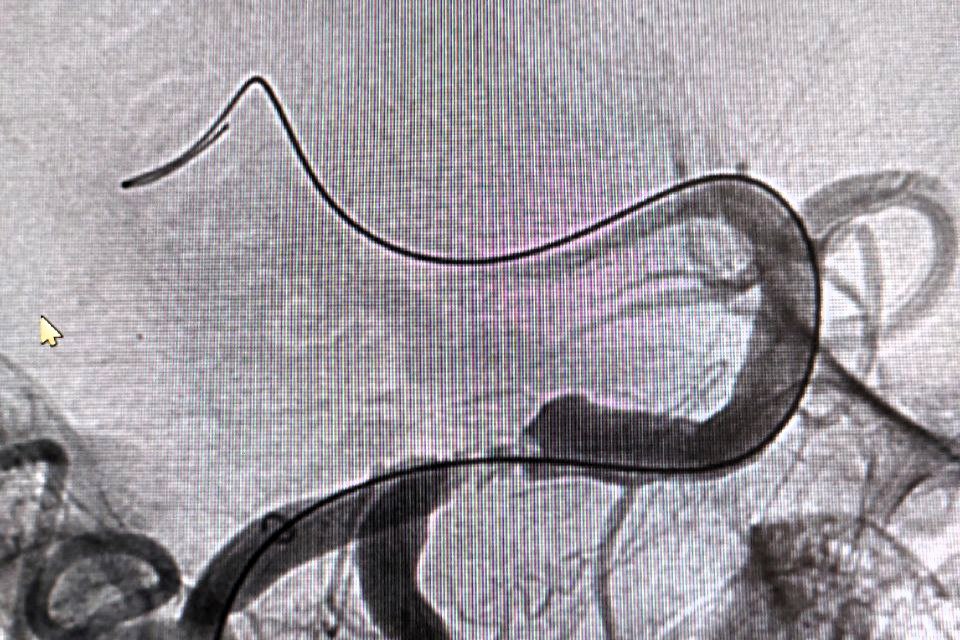

По словам заведующего отделением рентгенохирургических методов диагностики и лечения РСЦ Антона Аналеева, причиной стало образование атеросклеротической бляшки, перекрывшей главную артерию, снабжающую кровью ключевые участки мозга.

Благодаря вовремя поставленному диагнозу пациенту экстренно провели операцию, в ходе которой удалили тромб, а также установили стент.